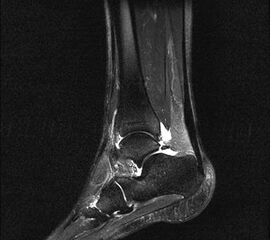

Hier befindet sich ca. 3-5 cm proximal des Tuber calcanei ein als „kritische Zone“ benannter Bezirk, der durch eine ungünstige arterielle Blutzufuhr gekennzeichnet ist (letzte Wiese). Hier finden sich häufig spindelförmige Schwellungen, die bei MRT-Diagnostik nicht selten partielle Nekrosen und Partialrupturen der Achillessehne aufweisen (Abb. 14).

Unabhängig davon können insbesondere chronische Insertionstendinosen der Achillessehne von Partialrupturen (Abb. 15) und erosiven Läsionen des dorsalen Fersenbeines begleitet sein.

Bildgebung

Die sonographische Diagnostik eignet sich primär zur Erkennung schmerzhafter Prozesse im Verlauf der Achillessehne und kann bei Bedarf durch Röntgen bzw. MRT ergänzt werden. Besonders bei längeren Verläufen und kräftigen spindelförmigen Schwellungen (>9mm, Normwert <5mm) im Bereich der kritischen Zone sollte ein MRT zum Ausschluss von Nekrosezonen und Partialrupturen vor Therapiebeginn veranlasst werden. Die sonographisch leicht zu erfassende Veränderung der Sehnendicke im mittleren Sehnenanteil ist ein guter Indikator für die Schwere der Erkrankung und die Beurteilung des Behandlungsverlaufes. Die sichtbaren Veränderungen am distalen knöchernen Ansatz der Sehne sind diskreter.

Insbesondere bei größeren Partialrupturen (Abb. 14) sollten operative Verfahren erörtert werden. Kleinere Partialrupturen sind der ESWT gut zugänglich, wie die beiden nachfolgenden Beispiele zeigen: